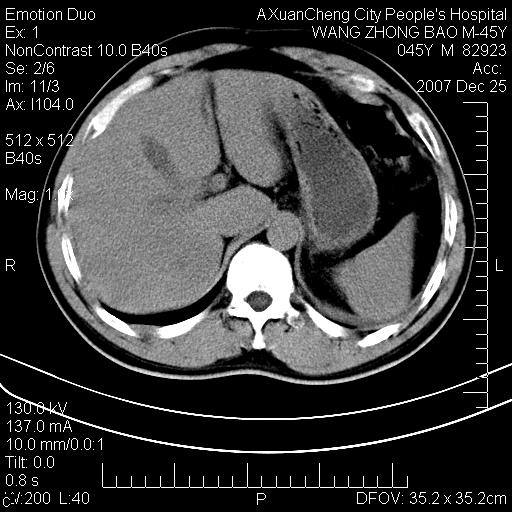

以下是引用qiuleiyu在2007-12-25 18:14:00的发言:[br]胰腺增大,周边渗出改变,肾前筋膜明显增厚,示少量积液.胆囊壁毛糙,周边少许渗出,胆总管壁厚,异常强化,然扩张不明显.结合病程急短;考虑;胆管炎,胆囊炎,胆源性胰腺炎可能大,请结合实验室检查及随访.

以下是引用lisihao在2007-12-25 14:23:00的发言:[br]急性水肿型胰腺炎[br]依据:1、胰腺弥漫性肿大,边缘稍毛糙;[br] 2、双侧肾周筋膜增厚,尤以左侧为甚(重要征象)[br] 3、双侧后胸膜增厚(刺激性炎症);[br] 4、结合病史,查血尿淀粉酶应该可以确诊。